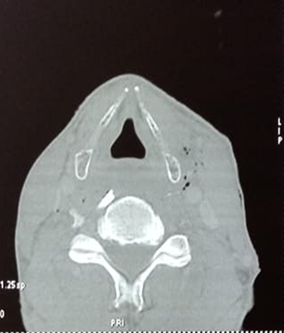

A cervical CT scan with injection of contrast product

was then carried out to assess the lesion and guide the treatment. It revealed

the presence of a prevertebral foreign body, but miraculously all the vascular,

digestive and aerial anatomical structures were intact (Figure 2).

Figure 2: CT scan showing the

presence of a prevertebral foreign body